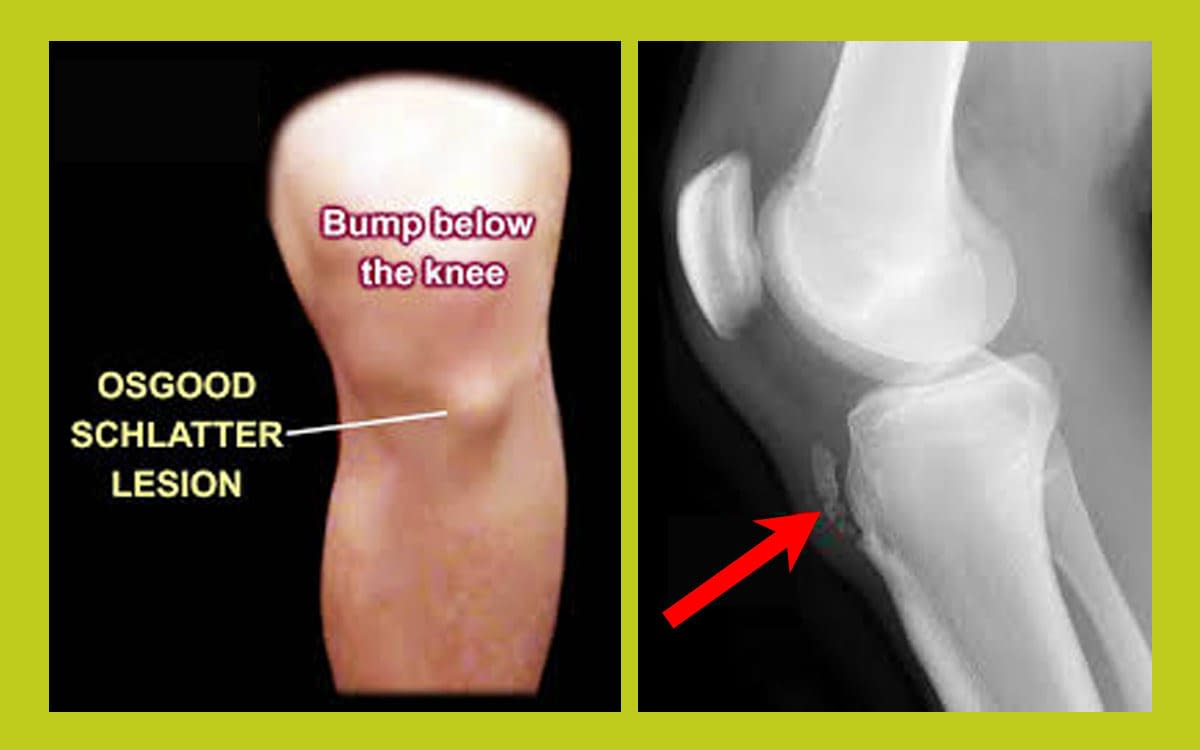

bump below the kneecap